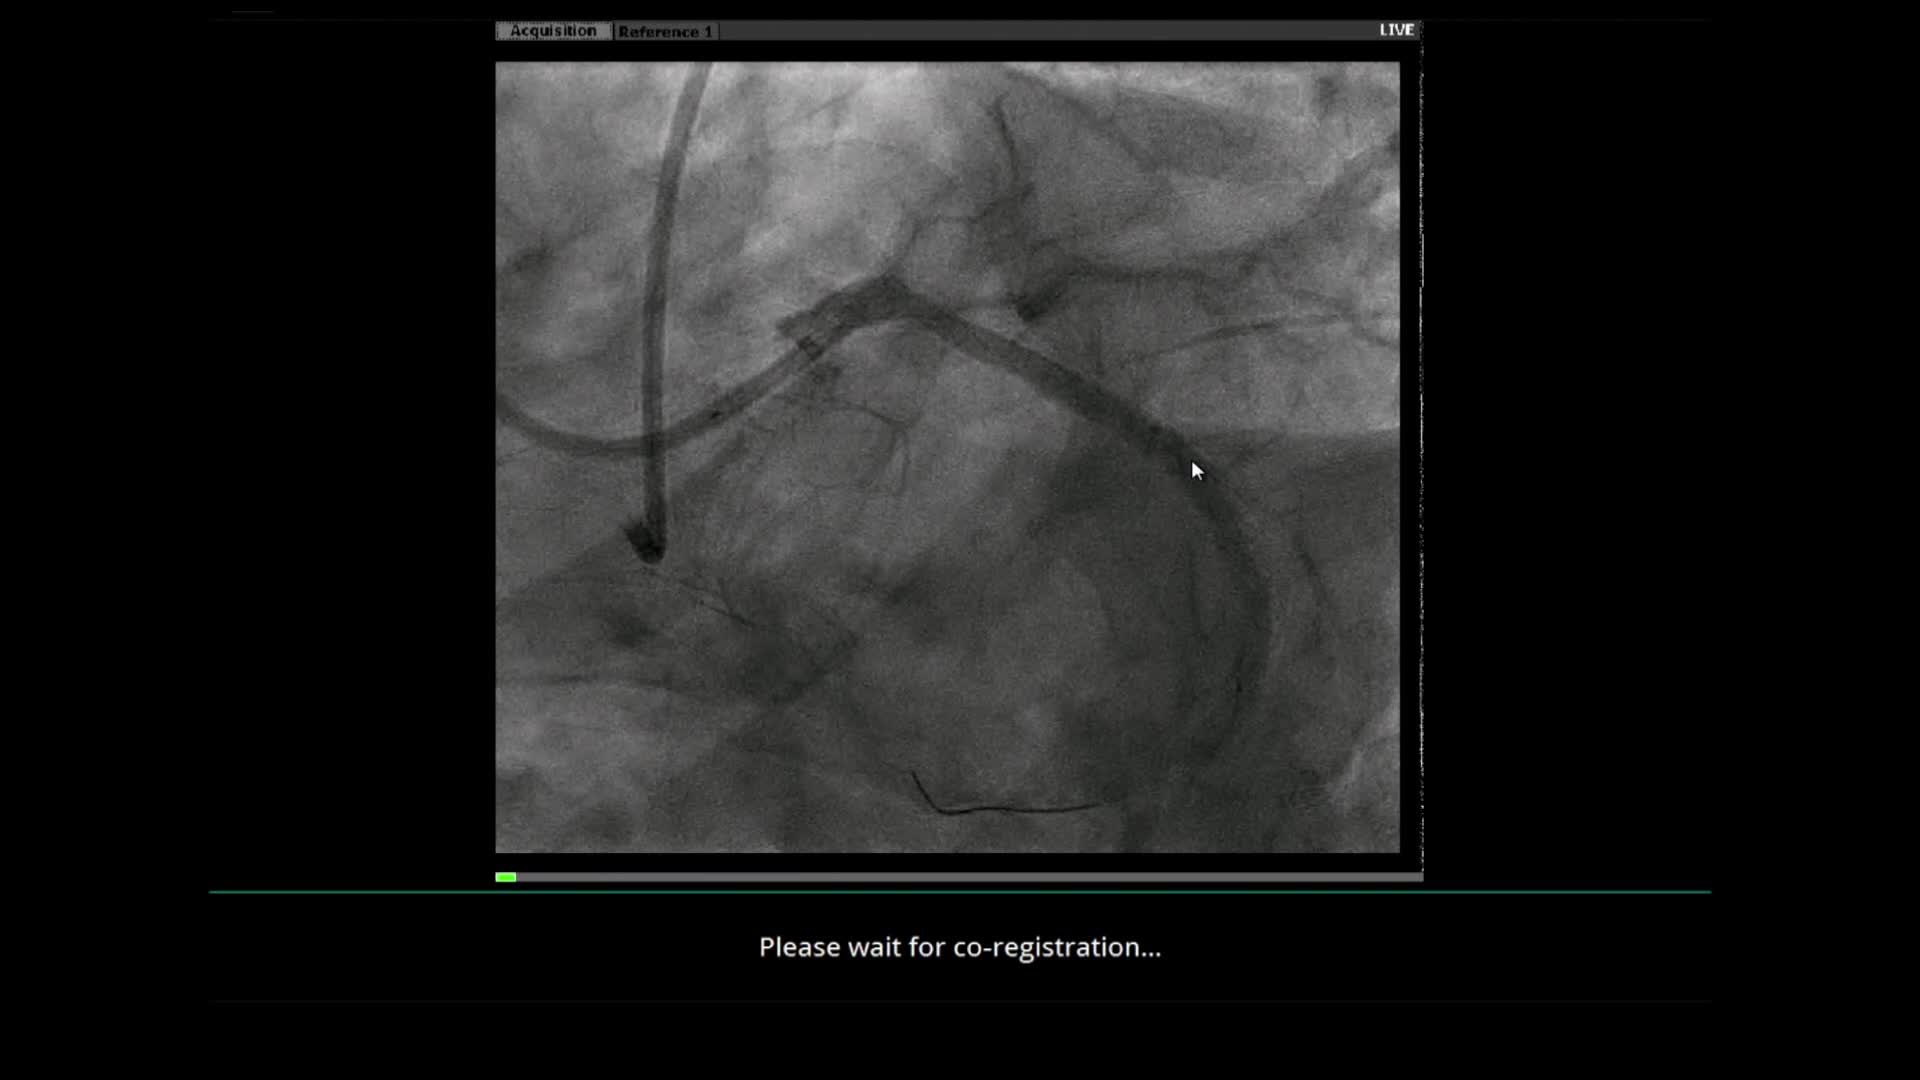

Dr. Raj Pyne Case Review: Popliteal CTO in CLI Patient

Case Courtesy of Dr. Raj Pyne | Rochester Regional Health | Rochester, NY